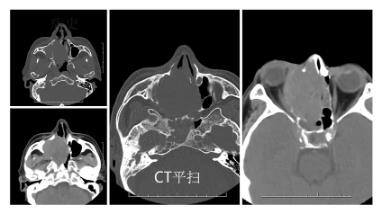

- 【02】磁共振病例分析-鼻腔恶性肿瘤